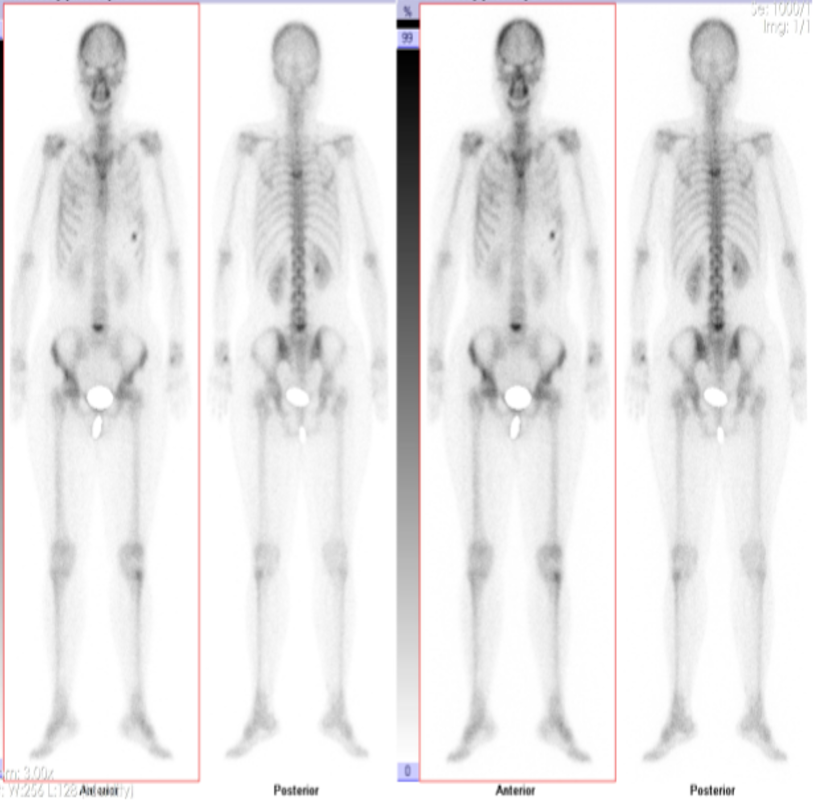

2023年2月,查胸部增强CT(图1)示:右肺下叶病变,伴部分肺实变,右侧肺门及纵膈内多发增大淋巴结,双肺多发磨玻璃结节。全身骨ECT(2022-03-03,图2)示:左6前肋骨代谢增高;T5、L5椎体骨代谢增高,结合病史提示骨转移。腹部CT、头颅MRI未见明显转移。

诊断方面,患者查胸部增强CT提示右肺下叶病变;全身骨ECT显示骨代谢增高,提示骨转移;腹部CT、头颅MRI未见明显转移。CT引导下经皮肺穿刺活检、超声支气管镜明确为肺腺癌,最终确诊为右肺腺癌(c-T2N2M1),基因检测提示TP53突变。